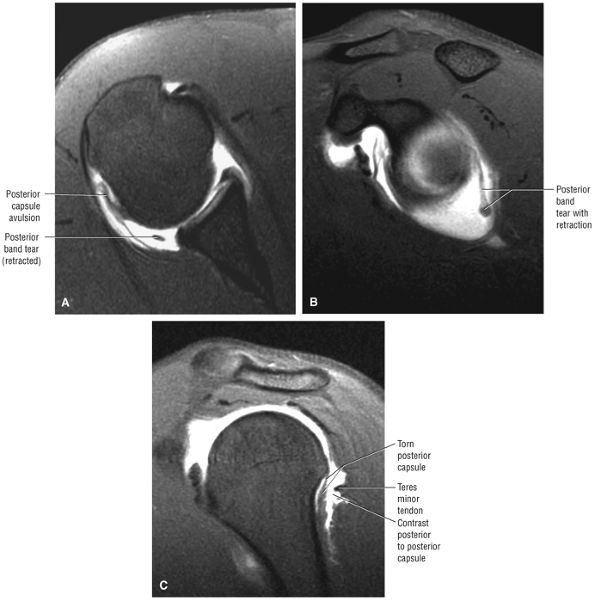

capsule, posterior dislocation does not occur even with division of the posterior capsule. The posterior capsule is torn in reverse HAGL lesions.73